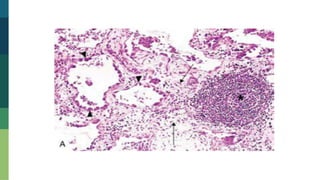

Tuberculosis

Granuloma

Granuloma Pulmonar

Inflamación Granulomatosa Patrón diferentede reacción inflamatoria crónica que se caracteriza por acumulación focal de macrófagos activados que pueden desarrollar una apariencia semejante a un epitelio, encontrándose en un número limitado de infecciones mediadas inmunológicamente. Ej. tuberculosis, sarcoidosis, enfermedad por arañazo de gato, linfogranuloma inguinal, lepra, sífilis, brucelosis, algunos hongos y reacciones por lípidos irritantes. El granuloma es un foco de inflamación crónica con presencia de macrófagos que se transforman en células semejantes en células epiteliales (células epiteliodes) las cuales se encuentran rodeadas por células mononucleares (linfocitos y Células plasmáticas). Las células epiteliodes se unen y forman las células gigantes